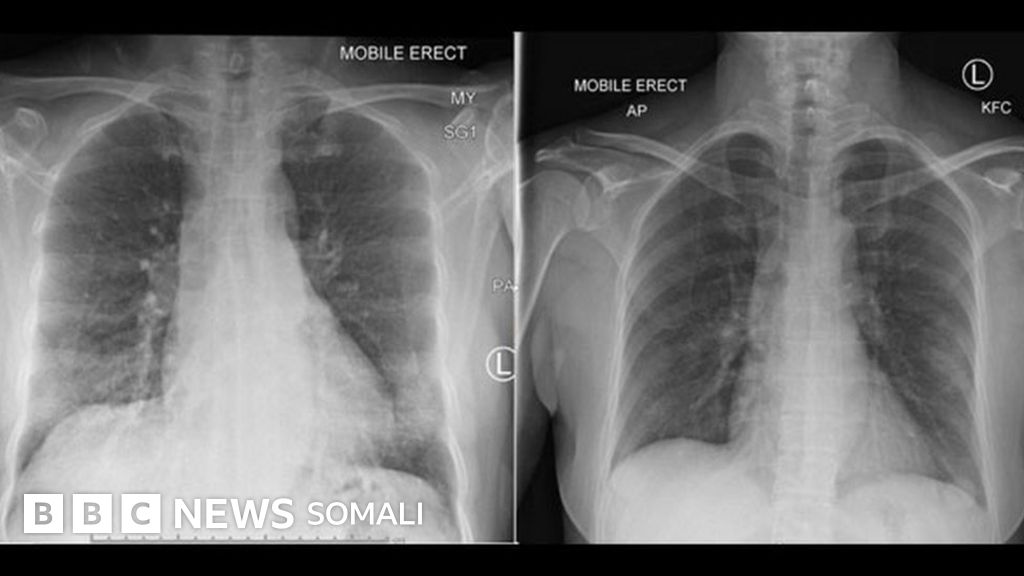

Xigashada Sawirka, PETER DOHERTY INSTITUTE

Qoraalka sawirka, Feeraha ayaa nadiif noqda marka uu difaaca jirka tallaabo u qaado la dagaallanka cudurka